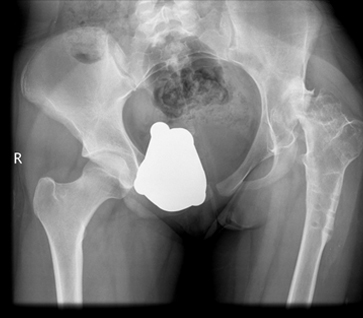

Some hips present with complex deformities. Examples are shown below. These hips often have had previous surgery resulting in severe stiffness or anatomical deformities. Others have significant congenital abnormalities like hip dislocation.

These are examples of complex hip replacements: